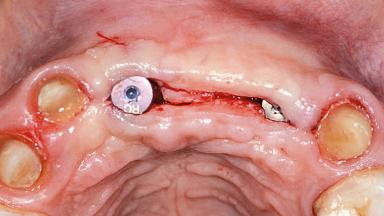

Replacement of Two Central Incisors and One Lateral Incisor with a Fixed Dental Prosthesis on Two Bone-Level Implants

A 38-year-old woman presented with an esthetically unacceptable fixed partial denture replacing teeth 11, 21, 22. She had lost these teeth due to trauma when she was a child. The patient was not in pain but very concerned based on her previous experience that dental treatments had never satisfied her esthetic expectations. She was in good general health and reported no regular medications. No periodontal disease was noted despite the fact that the buccal flange of the prosthesis impeded cleaning of the tooth abutments. The patient did not smoke and complied with home maintenance requirements, as evidenced by her good oral hygiene status.

Bone Volume | Deficient horizontally, requiring prior grafting |

Soft Tissue Contour and Volume | Significantly deficient |